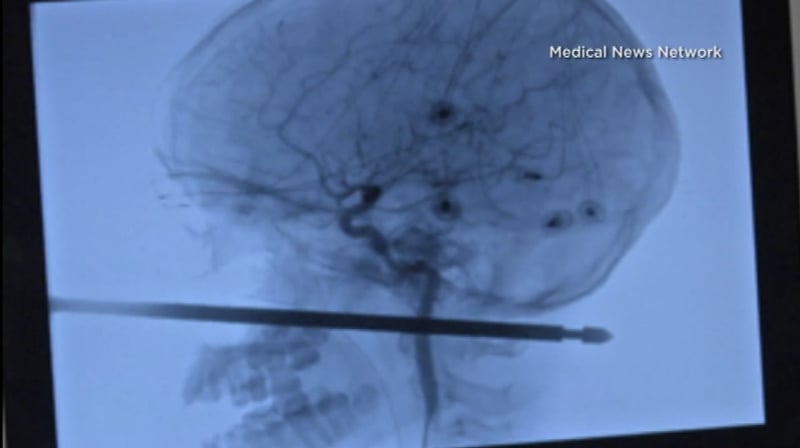

Instead, he is getting back on his feet in the Midwestern state of Kansas following surgery on Sunday to remove the 30cm skewer embedded from his cheekbone to the back of his neck.

"This thing had spared the eye, spared the brain, spared the spinal cord," neurosurgeon Koji Ebersole, head of the local university health authority, told the Kansas City Star.

"It was one in a million for it to pass five or six inches (13-15 centimeters) through the front of the face to the back and not have hit these things," he added.

Dr Ebersole said the skewer plunged through a tiny space in his head surrounded by major blood vessels.

The skewer pierced his left cheek below the eye and went clean through his skull, without piercing the skin in the back of the neck.